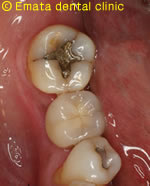

右下の奥歯が抜歯になりました。隣の歯は健康な歯なので削ってブリッジにすることを避けたいとの希望でした